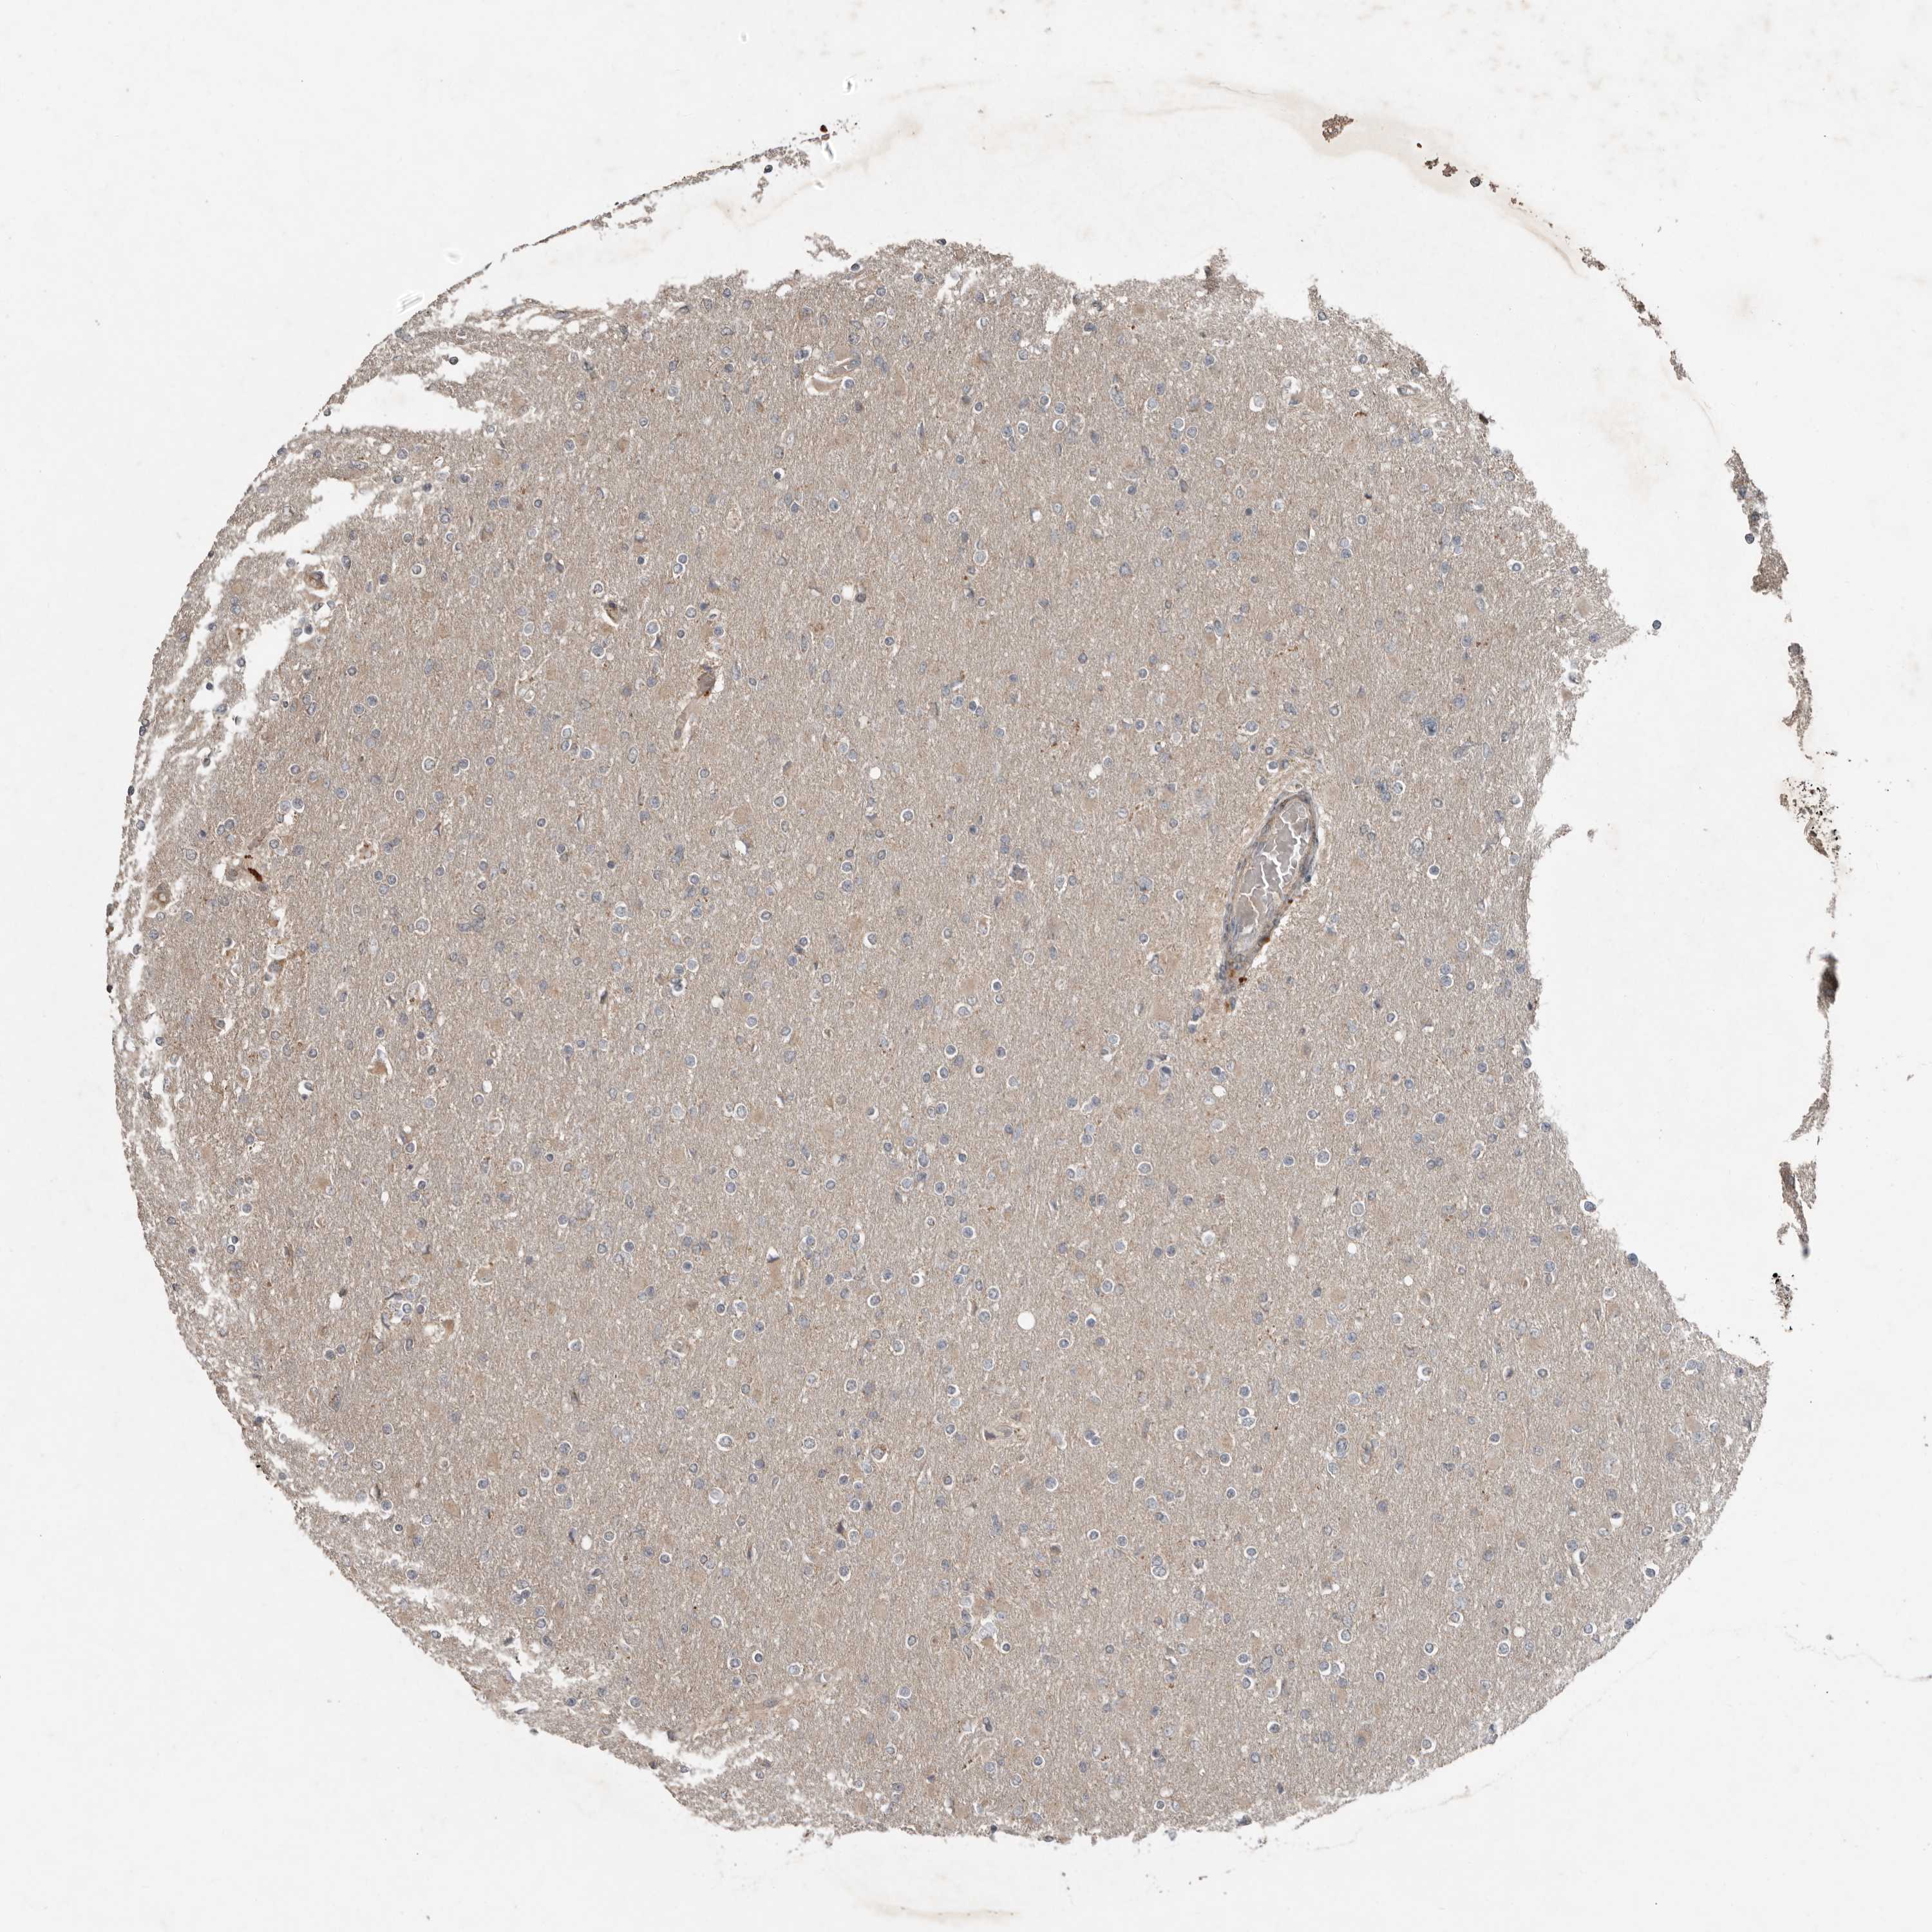

GLIOMA - Protein expressioni

A mouse-over function shows sample information and annotation data. Click on an image to view it in a full screen mode. Samples can be filtered based on level of antibody staining by selecting one or several of the following categories: high, medium, low and not detected. The assay and annotation is described here.

Note that samples used for immunohistochemistry by the Human Protein Atlas do not correspond to samples in the TCGA dataset.

Antibody stainingi

Antibody staining in the annotated cell types in the current human tissue is reported as not detected, low, medium, or high, based on conventional immunohistochemistry profiling in selected tissues. This score is based on the combination of the staining intensity and fraction of stained cells.

Each image is clickable and will lead to virtual microscopy that enables deeper exploration of all samples and also displays staining intensity scores, fraction scores and subcellular localization as well as patient and tissue information for each sample.

Antibody HPA028907

Staining

High

Medium

Low

Not detected

Intensity

Strong

Moderate

Weak

Negative

Quantity

>75%

75%-25%

<25%

None

Location

Nuclear

Cytoplasmic/membranous

Cytoplasmic/membranous,nuclear

Glioma, malignant, High grade

Glioma, malignant, Low grade